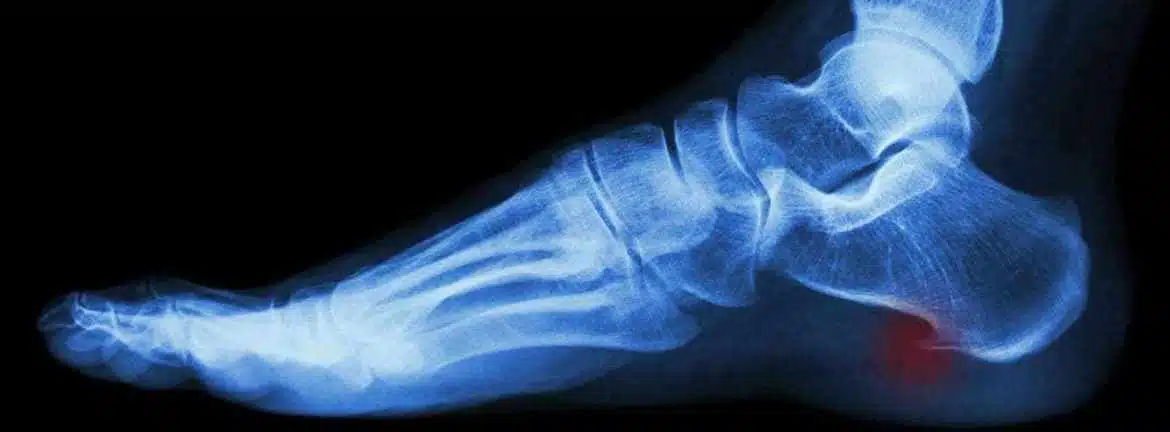

هي عبارة عن ترسبات من الكالسيوم تتكون في العظام هي حالة صحية تصيب العظام وتتسم بظهور نتوء عظمي إضافي على أطراف العظام وعادة ما يحدث في مناطق تلاقي العظام مع بعضها مثل المفاصل.

تسبب الشوكة العظمية مزعجة وقد تؤثر على الحياة اليومية للمصابين فعندما يكون الشخص مصابًا بالشوكة العظمية، يشعر بالألم والتورم في المنطقة المصابة، وخاصة حول المفاصل مثل المفصل الباطني للقدم ومفصل الكاحل وقد يشعر المريض بصعوبة في المشي.

هي المعروفة في المجال الطبي أيضاً باسم شوكة القدم هي حالة طبية تصيب الكعب القدم وتتسبب في آلام حادة ومزعجة، تكون الشوكة العظمية نتيجة لتشكل نسيج عظمي زائد على الكعب

- الشوكة العظمية: هي أحد أنواع الالتهاب التي تصيب القدم وتكون نتيجة لعدة أسباب منها وجود كالسيوم زائد في الجسم مما زاد من الرواسب فيه وبالتالي تأثر الجسم به، وتبدأ الشوكة العظمية في الظهور كنتوء في القدم يمد حتى الكعب مما يسبب صعوبة في المشي.